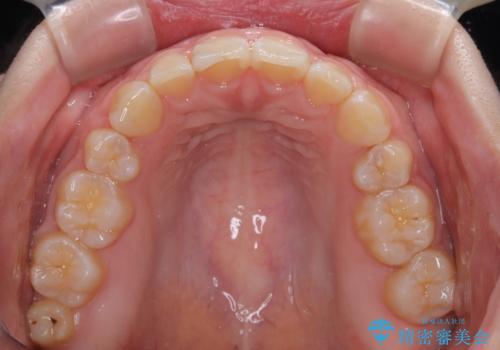

- 出っ歯と口の閉じにくさ、デコボコを気にして来院された患者様です。

口元の突出感を改善するため、上下左右第一小臼歯4本の抜歯を行い、ワイヤー装置による矯正治療を行うこととしました。

抜歯矯正を行ったことで、顎先のつっぱり感や口元の閉じにくさを解消することができました。